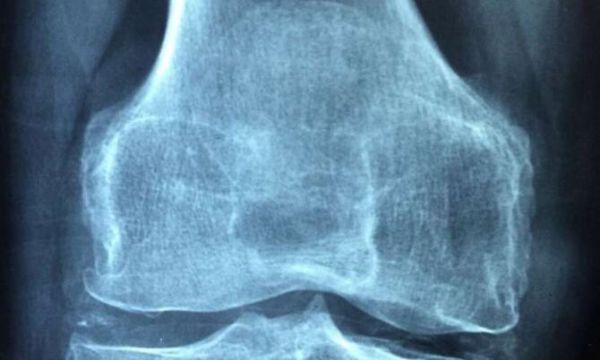

目前研究人员识别出了多种类风湿性关节炎小鼠模型,但对于中轴型脊柱关节炎(AxSpA,axial spondyloarthritis)模型而言却数量非常有限,胶原蛋白Ab所诱导的关节炎(CAIA)是科学家们使用最广泛的关节炎小鼠模型之一,其具有补体依赖性。近日,一篇发表在国际杂志Immune Network上题为“A Potential New Mouse Model of Axial Spondyloarthritis Involving the Complement System”的研究报告中,来自科罗拉多大学等机构的科学家们通过研究发现,患有一种自身免疫性疾病或会导致另外一种疾病的发生。科学家们偶然间发现,患有抗体诱导的类风湿性关节炎的小鼠的关节会继续发展处于AxSpA小鼠类似的脊柱病变,AxSpA会导致机体脊椎融合和脊柱弯曲等病理学表现。

研究者Nirmal Banda博士表示,本文研究结果表明,诸如类风湿性关节炎等自身免疫性疾病会导致另一种诸如AxSpA的自身免疫性疾病的发生,这种有趣的疾病关联或许是由于抗胶原蛋白自身抗体与脊柱的结合,或免疫系统所发生的某些改变,这或许还需要进一步研究。这些相同的抗胶原蛋白抗体同样也存在于关节炎患者机体中,其会直接攻击关节软骨并导致炎症和疼痛的发生。研究者表示,每只注射抗体所诱导的关节炎(CAIA)的小鼠都会患上关节炎,随后出现与AxSpA相一致的脊柱弯曲;研究人员刚开始注意到脊柱中的骨质增生和椎体的融合,在某些位置,脊柱椎体之间的正常空间或许正在消失,而这与患AxSpA的人类机体所发生的情况类似。

研究人员认为,由于环境的不断变化,于是患自身免疫性疾病的患者数量在不断攀升,牙龈疾病和类风湿性关节炎、萎缩性增龄性黄斑变性和类风湿性关节炎之间或许都存在一定关联,这或许是后期需要研究人员进一步研究探索的领域;综上,本文研究结果表明,研究人员描述了一种与CAIA诱导相关的新型临床前小鼠模型,这类小鼠会表现出AxSpA的突出特征,而这种新型的AxSpA实验模型或许能帮助研究人员阐明AxSpA骨骼和软组织发生改变的局部因果关系和机制,以及帮助后期开发新型靶向性疗法。